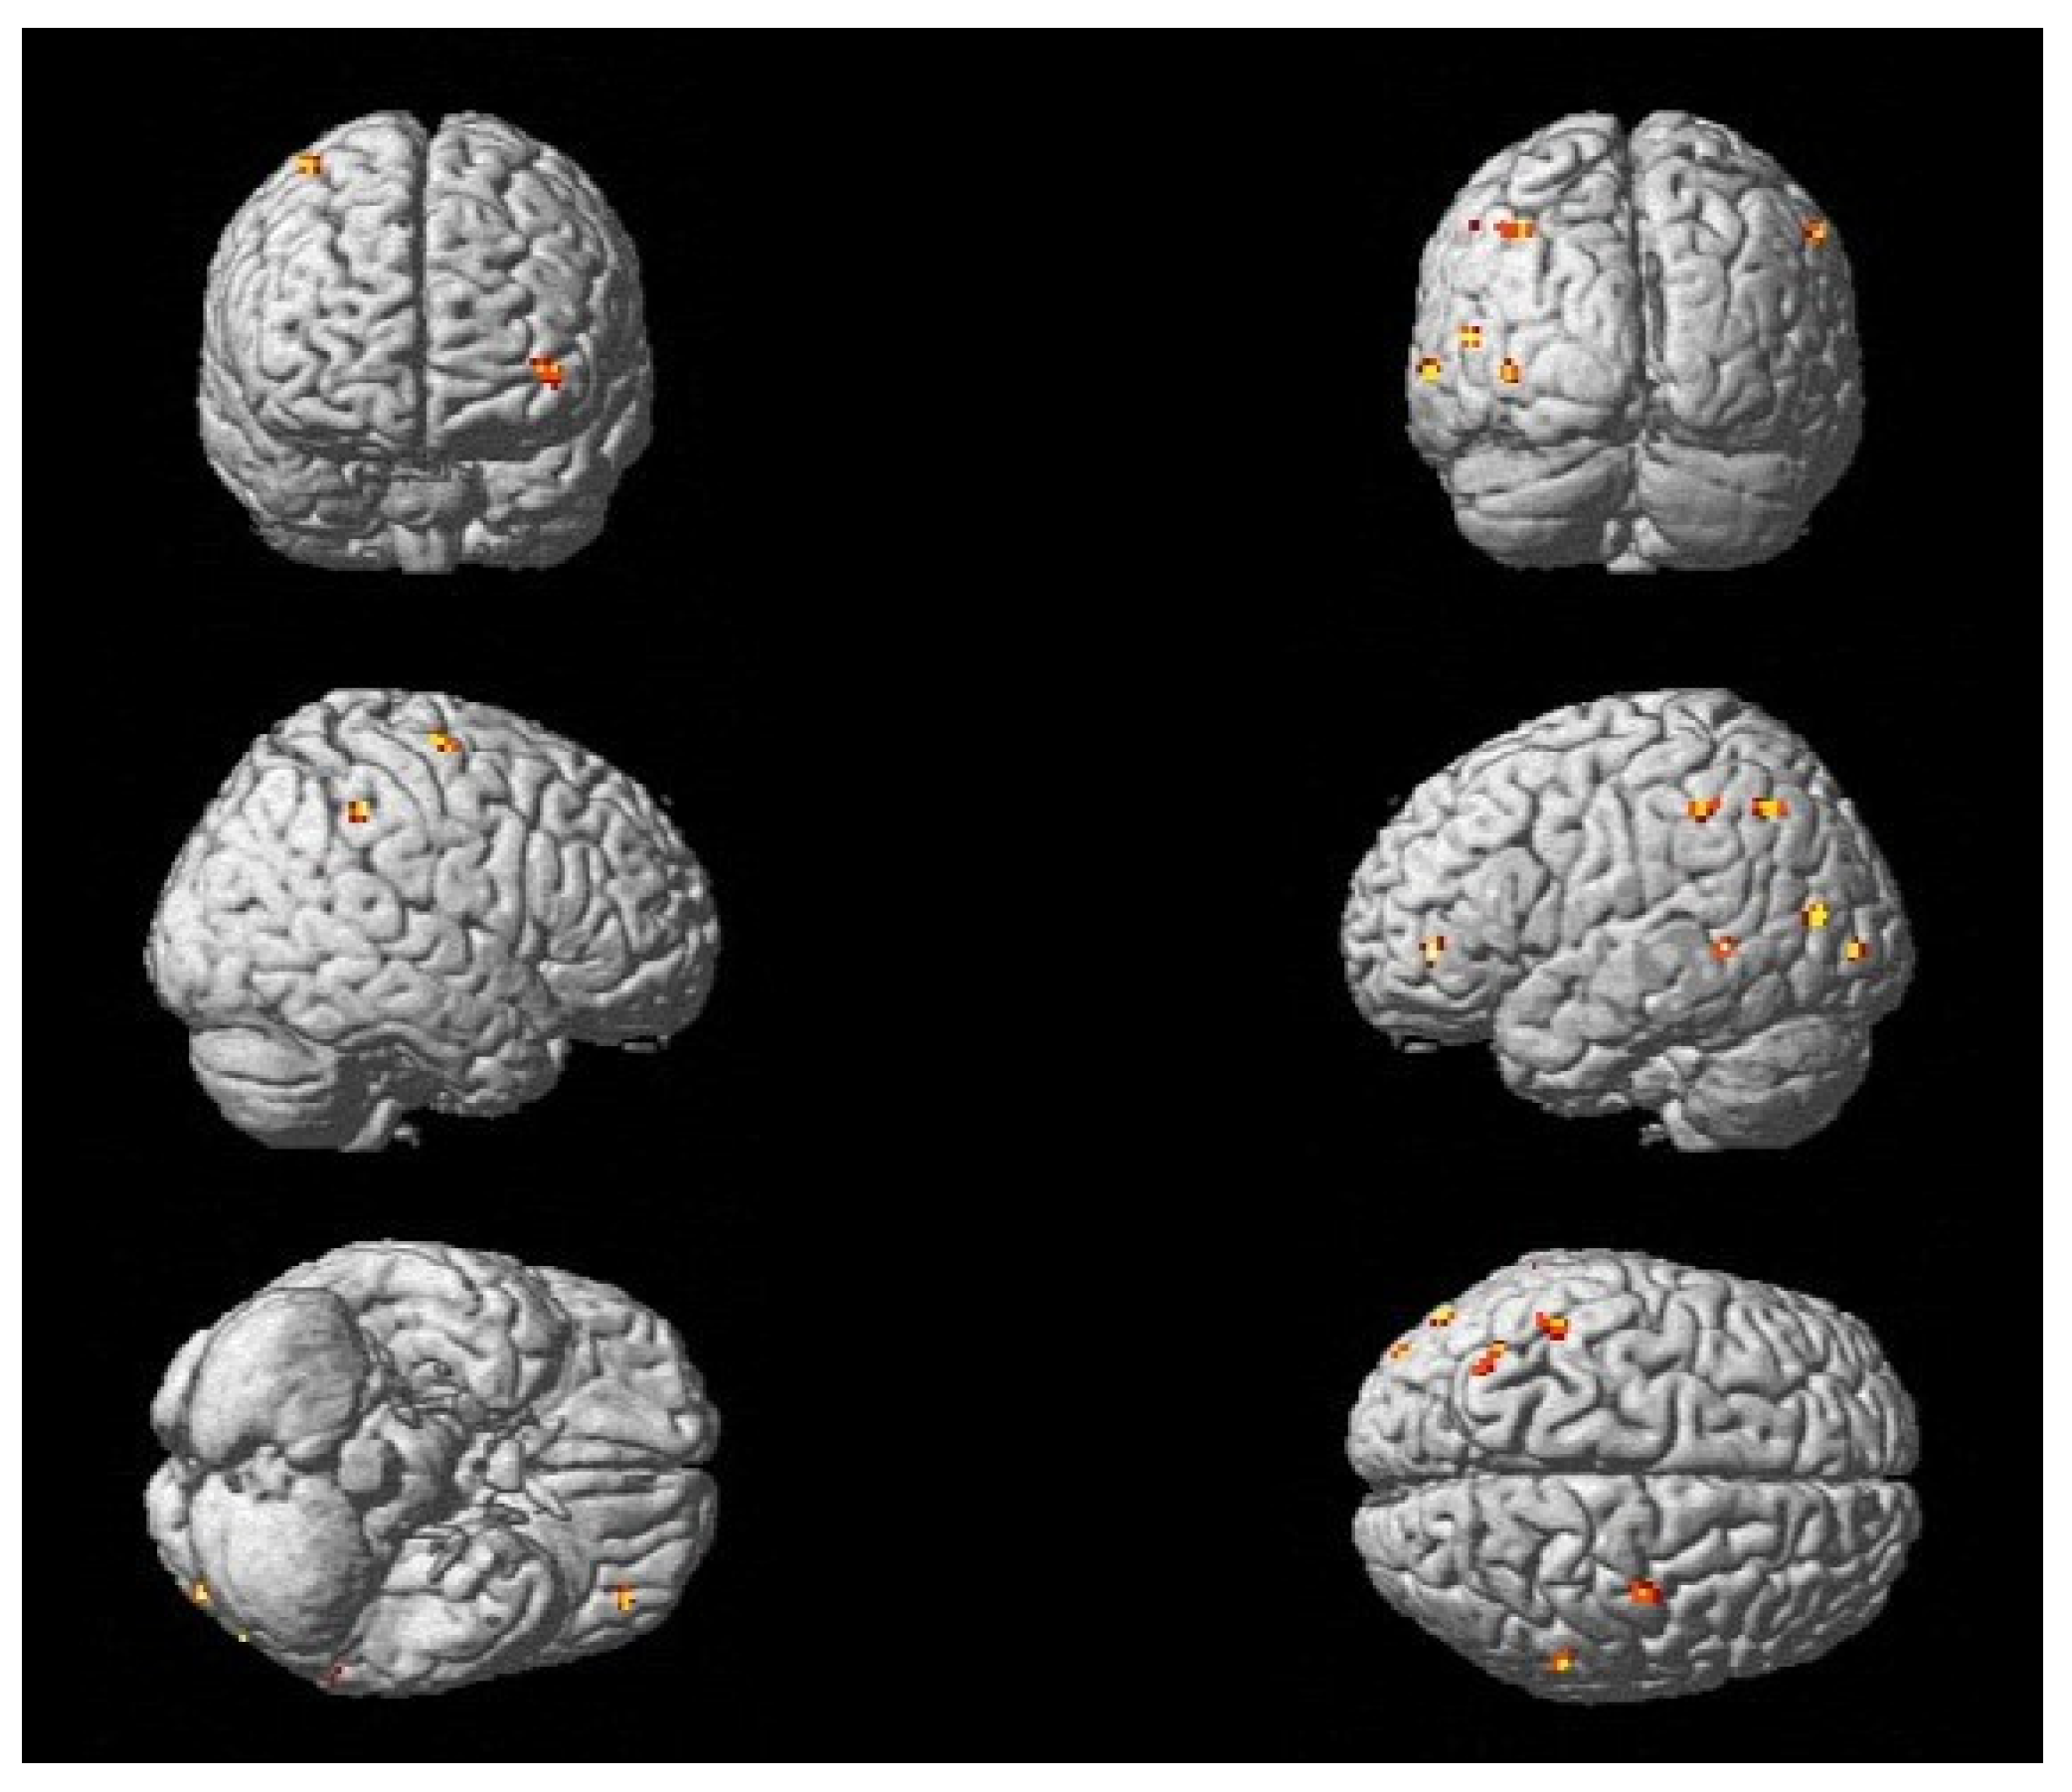

3.2. Changes in Activation Patterns During Recovery and Rehabilitation